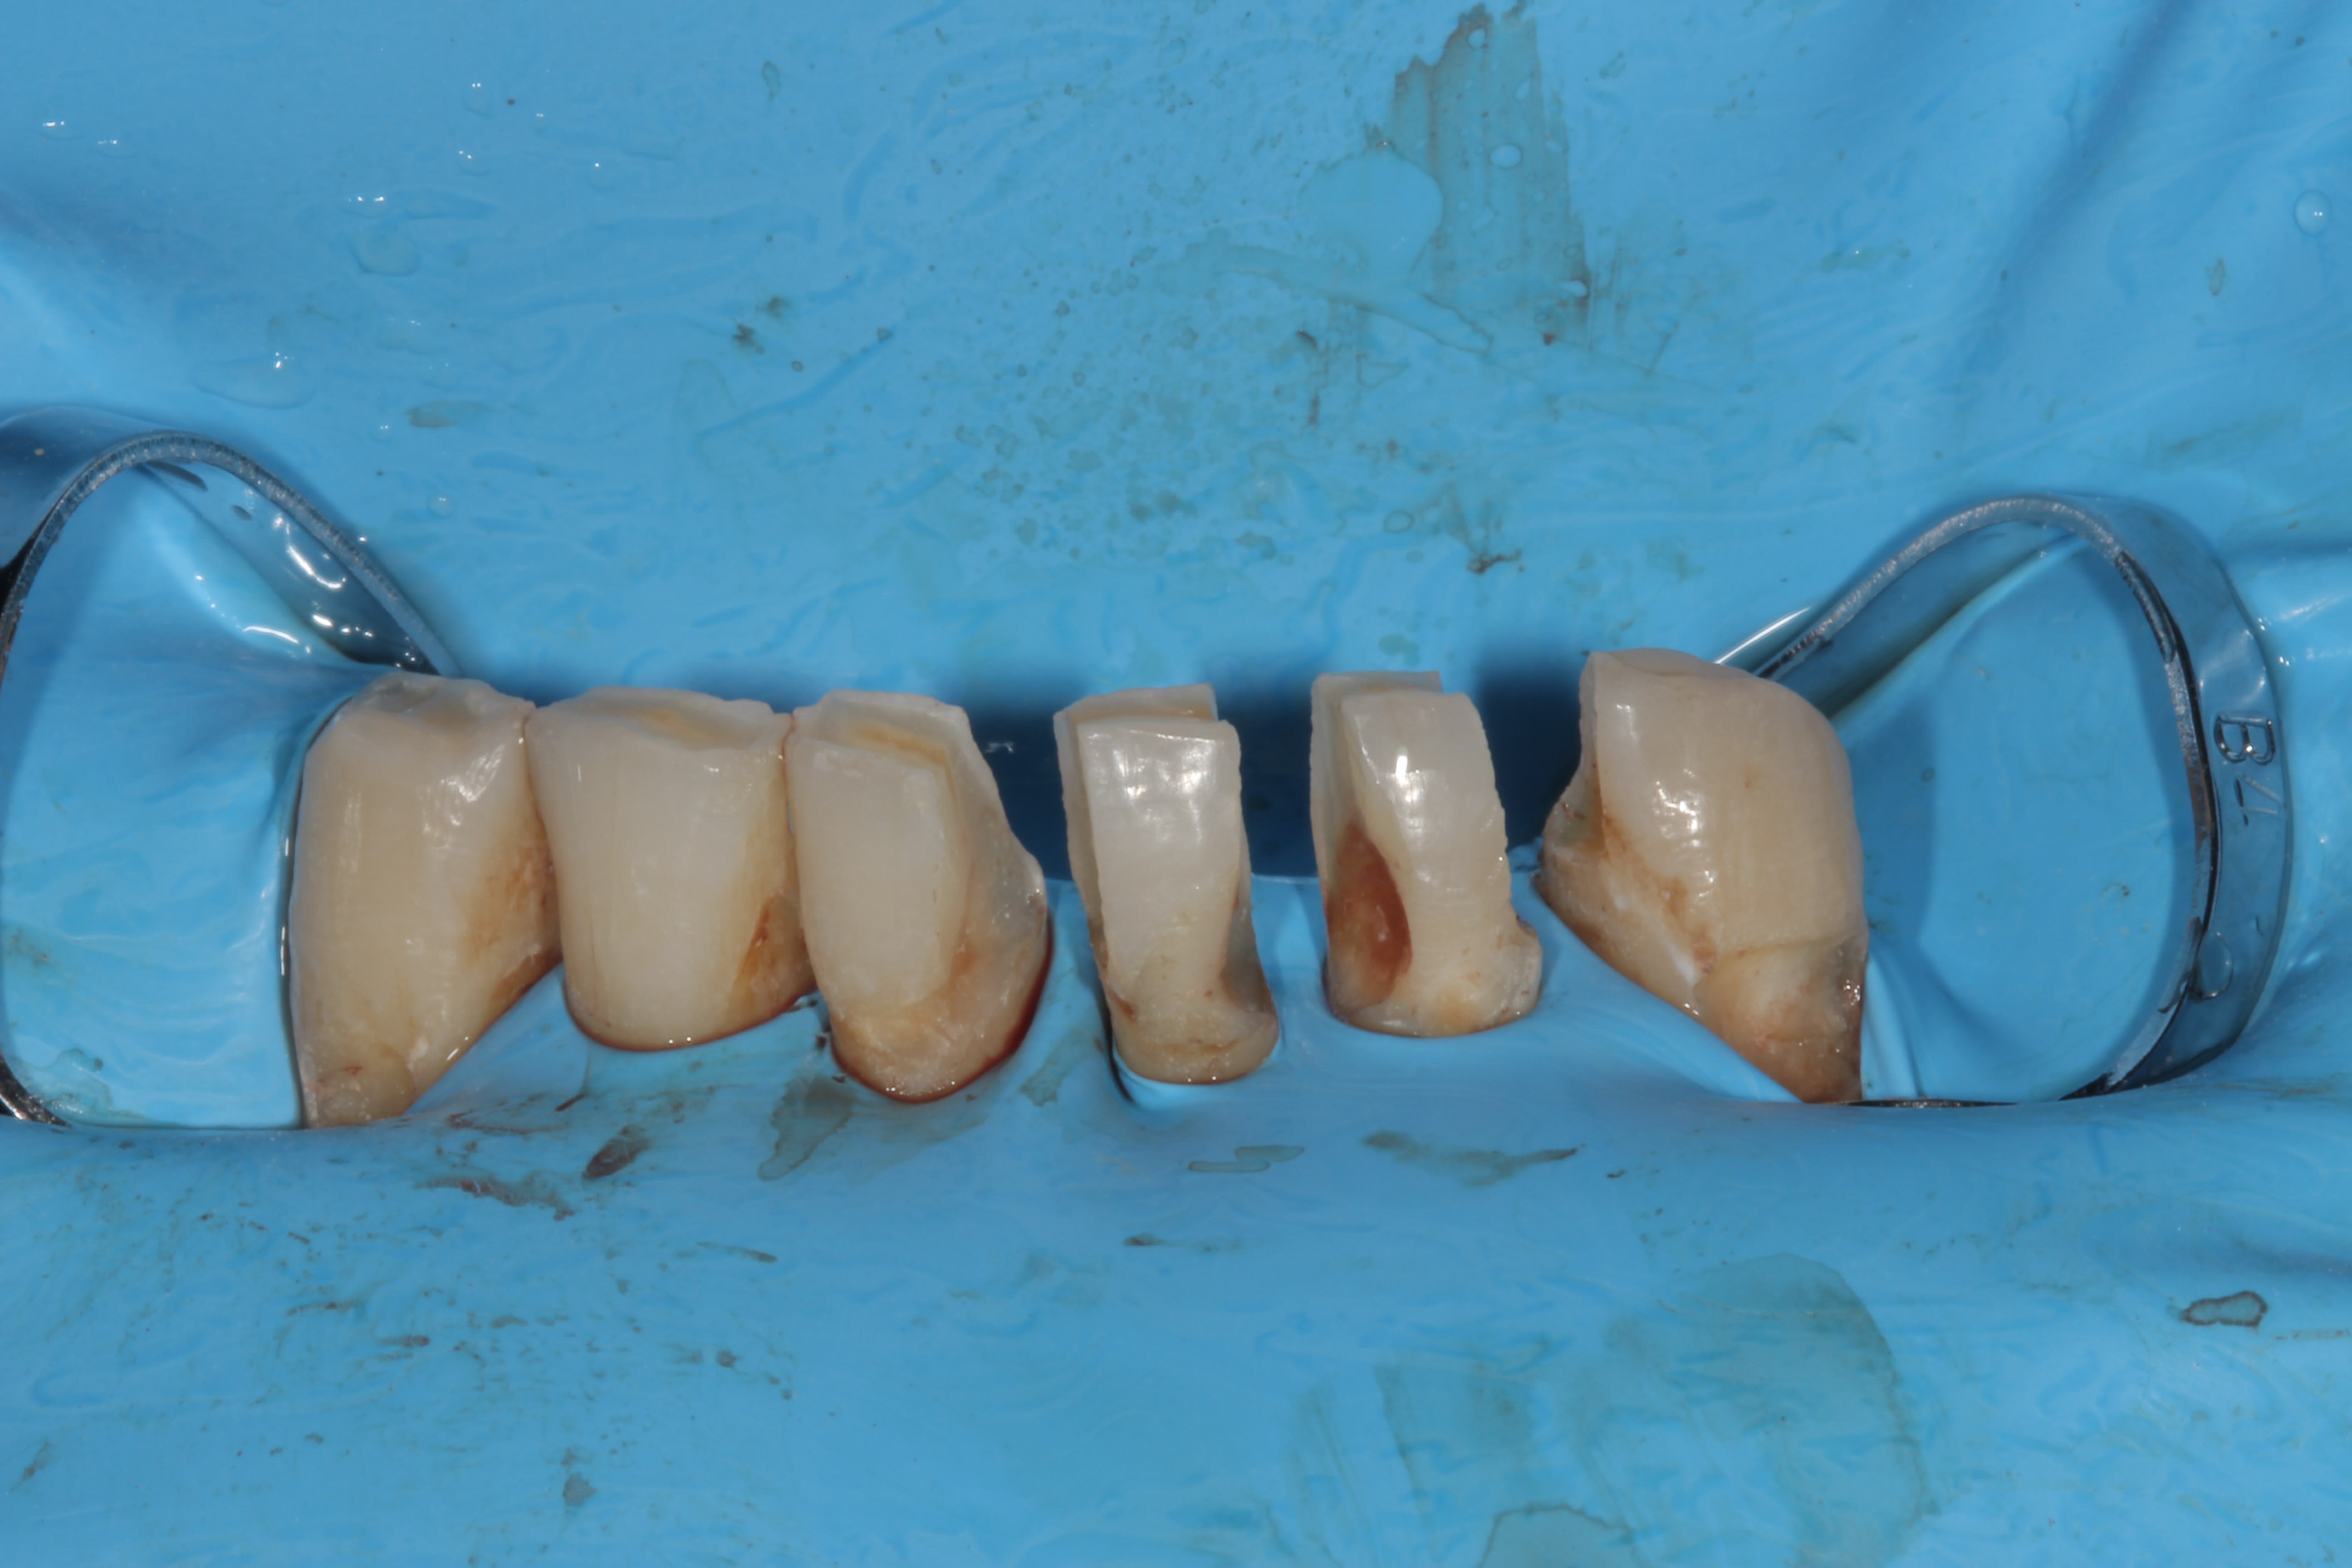

En tout cas, tu es motivé et tu fais de beaux compos.

le patient est asymptomatique, je ne vois pas la raison pour dévitaliser. Mon idée est de faire comme dit précédemment, des couronnes préventives. Soyons honnêtes, laisser des composites dans ce milieu buccal ne donnera pas de bons resultats, il faut une protection périphérique.

Enlever l' email ne va pas fragiliser la dent. De la dentine oui. C' est la raison pour laquelle je ne fais pas de congé ou autre mais des préparations verticales, pour maintenir de la dentine pericervicale.

Je garde de la ferrule et il devrait pas y avoir de probleme. maintenant, je l' ai déja dit, je n' ai pas une expérience de X0 années . Juste quelques années. Mais dans ma pratique actuelle, c' est ce que je fais. Apres, pour ce qui est des photos avec les cavités, ce ne sont pas les prepas finales, il y a surement eu une reduction des murs fins/fragiles.

c' est vrai que j' avais tendance a preparer a minima et que mon protho me demandais plus d' espace. depuis je me suis un peu amelioré =).